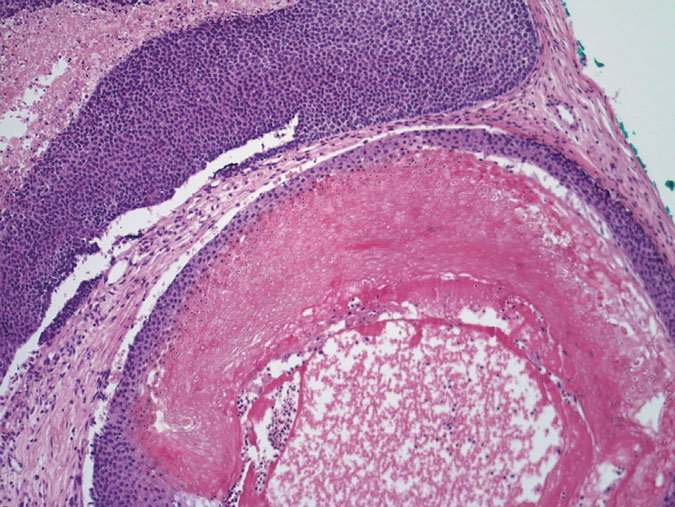

Pilomatricoma shows a spectrum of morphologic features that mainly reflect different evolutionary stages. Early and well-developed pilomatricomas reveal variably sized, round to oval cystic lesions lined by a basaloid epithelium at the periphery and filled in the center with masses of eosinophilic, faulty hair matrix material containing “shadow” (“ghost”) cells

Basaloid (matrical) cells show monomorphous round nuclei with one or more distinctive nucleoli and variable numbers of mitotic figures. Foci of squamoid epithelium are sometimes noted within the epithelial lining. Regressing pilomatricomas display haphazardly arranged foci of basaloid cells and shadow cells as well as an inflammatory infiltrate with multinucleated histiocytic giant cells. Granulation tissue is sometimes noted. Old pilomatricomas reveal no basaloid component but show irregularly shaped, partially confluent masses of shadow cells with foci of calcification or ossification. Melanin deposition, trans-epidermal elimination, and extramedullary hematopoiesis have been described in some pilomatricomas. A peculiar variant with relatively large areas of basaloid cells and small foci of shadow cells (“proliferating pilomatricoma”) is occasionally observed in older adults.